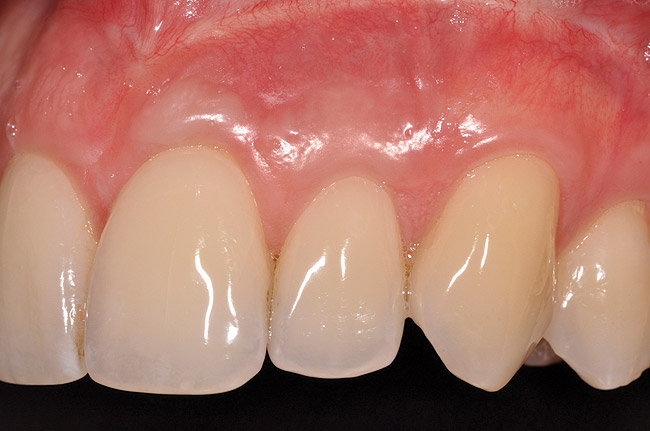

Once the flap was coronally repositioned and secured, a securing periosteal tac procedure was performed to prevent any micro movement superior to the mucogingival junction in the initial healing phase. A 4.0 chromic gut suture (Surgical Specialties Corp.) was used to engage the periosteum superior to the mucogingival junction and stabilize the tissues superior to the securing suture (Figure 12 and Figure 13). Multiple periosteal tac sutures may be necessary, depending on the size of the surgical field. Postoperatively, the periosteal tac sutures are routinely removed if not totally absorbed at 7 days; the flap sutures are removed at 2 to 3 weeks, and dermal-securing sutures are removed 1 month after surgery. The 1-year post-treatment clinical view shown in Figure 14 depicts the excellent soft-tissue result, band of attached–keratinized tissue present, and excellent color match to the host gingival tissues.

Fig 14. One-year postoperative view of case presented.

Figure 14